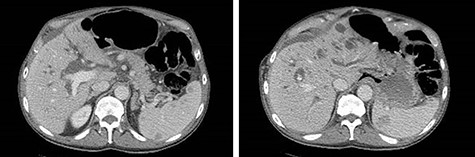

Exploratory laparotomy revealed a massively dilated cecum and right colon with complete 360-degree clockwise rotation along the ileocolic pedicle. The right colon and cecum were eviscerated from the abdomen (Fig. 3). The colon was viable, but extremely dilated and thin walled. The proximal region of the volvulus was identified, and the distal ileum was divided. A decompressed region of transverse colon was identified as the distal region of the volvulus. There were extensive adhesions involving the afferent biliopancreatic limb and the gastrojejunal anastomosis to the transverse mesocolon. Once mobilized, the transverse colon was divided to the right of the middle colic vessels. The specimen was detorsed immediately prior to division of the ileocolic pedicle, and ileocolic anastomosis was performed. Four small (<2 cm) uninvolved peritoneal implants were identified, removed and sent for permanent pathology.